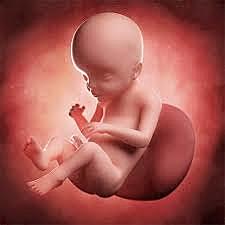

• Semana 12

27

Semana 12

Cuello bien definido, oído externo bien definido, saco vitelino se ha retraído, expulsión de meconio, ovarios descienden, sangre se puede coagular.